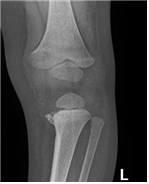

아동 학대를 의심해야하는 골절

• 매우 드물거나 불가능한 골절

• 다발성 두개골 골절

• 다발성 늑골 골절 (shaken baby syndrome)

• 모양 자체로 의심스러운 골절

• 걷지 못하는 아이의 팔/다리 나선형 골절

• 골간단모서리 골절 (metaphyseal corner fracture, “bucket handle”fracture)

• 오래된 골절, 보호자가 언제 생겼는지 모르는 골절 (가골이 보임)

• 드문 부위 골절